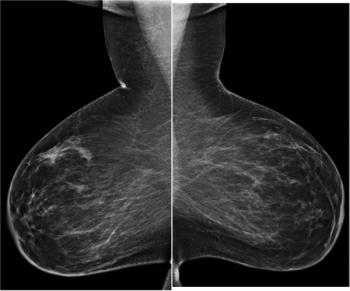

50-year-old patient presented for screening mammogram. Extremely dense breast tissue was noted.